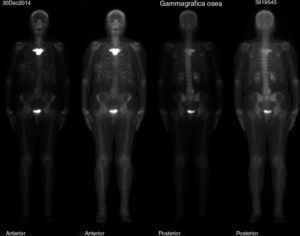

En el estudio de extensión de la enfermedad solicitado, se evidenció imagen gammagráfica de lesión blástica, difusa, en el manubrio esternal, sospechosa de enfermedad de Paget o de lesión metastásica (fig. 1). Se completó el estudio con radiografías de tórax, columna lumbosacra y pelvis (figs. 2 y 3), en las que solo se evidenció aumento de densidad interapofisaria de L4 y L5. Posteriormente, se solicitó TC torácico, según recomendaciones de Medicina Nuclear, que informó de esclerosis en el manubrio esternal, sugerente de metástasis (fig. 4).

En nuestro caso, el estadio tumoral de la paciente (estadio IA) y las características fenotípicas indicaban que el resultado del estudio de extensión que informaba de posible metástasis esternal en el carcinoma de mama podría ser puesto en duda. Así pues, se valoraron posibles alternativas diagnósticas que pudieran explicar estos hallazgos. Conocer el síndrome de SAPHO, aunque sea una entidad clínica de baja incidencia, puede evitar clasificar como metastásico al paciente que presenta la imagen característica de «asta de toro» en la gammagrafía ósea. Si esta imagen se hubiera presentado en un paciente con factores de mal pronóstico, probablemente no se habría dudado de la posibilidad de lesión metastásica y, por ende, hubiera sido subsidiaria de tratamiento quimioterápico (vinorelbina o taxanos) y de un tratamiento radioterápico más agresivo, con las complicaciones que ello conlleva.